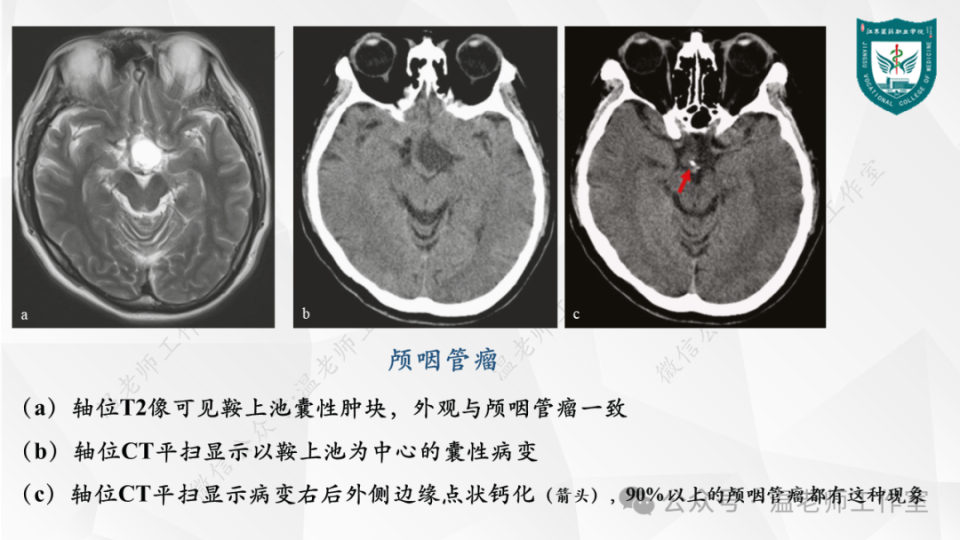

中枢神经系统的病例影像:脑肿瘤

图片尺寸960x540